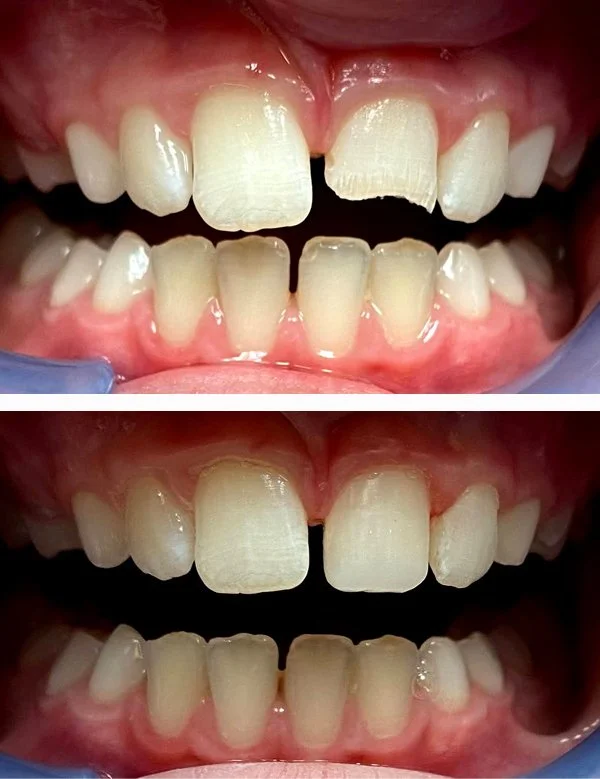

Tooth Fracture